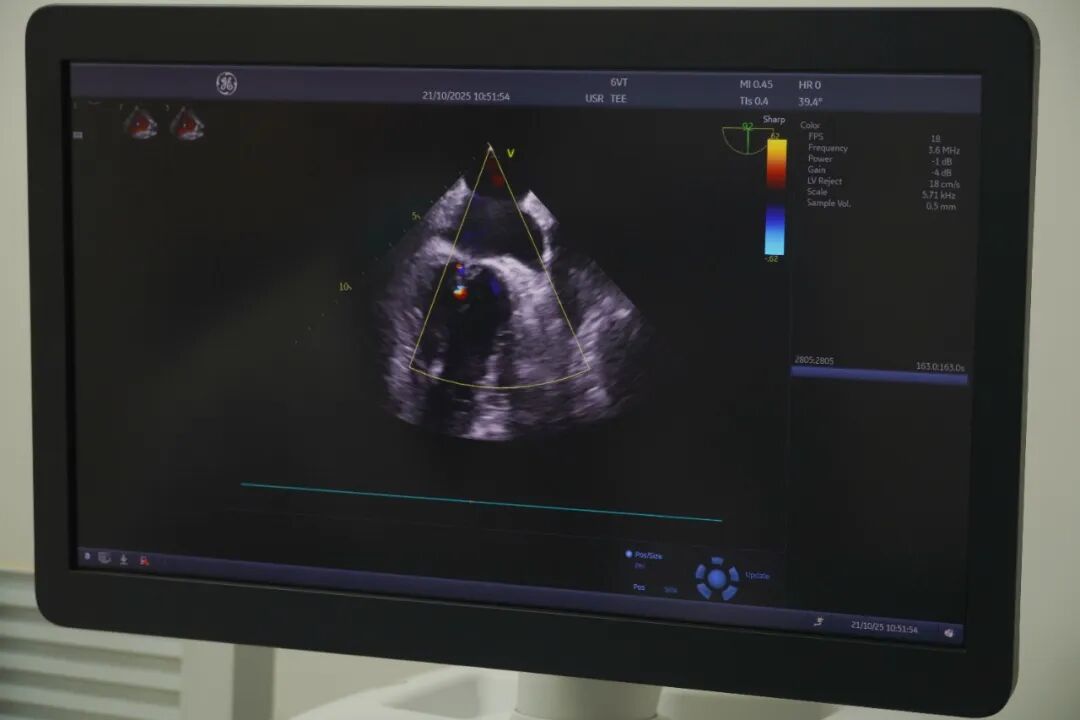

九江新闻网讯(杨书锦)近日,湖口县总医院人民医院院区超声科顺利完成首例经食道超声心动图检查,标志着医院心血管疾病诊断水平迈上新台阶。此项技术的开展,提升了超声心脏疾病检查的高度和精准度,为临床诊断提供了更为准确的依据;也填补了县域该技术空白,让本地百姓无需远行,在家门口就能享受到与上级医院同质化的精准医疗服务。

此次接受检查的患者,是一位有着6年多房颤病史的患者,需要在医院准备接受心脏射频消融术。术前,超声科为他进行了一项关键检查——经食道超声心动图,其核心目的,正是为了精准排除心脏“左心耳”内是否存在血栓。这一步骤,是确保手术安全、降低卒中风险的生命防线。

常规胸前心脏超声因受骨骼、肺气干扰,难以清晰显示左心耳。而经食道超声心动图将高清探头经食道送至心脏后方,实现了对左心耳结构和血栓的“零距离”精准侦察,成为国际公认的、房颤消融术前排除血栓的“金标准”和必备检查。经食道超声心动图不仅是为房颤患者术前排除血栓的“侦察兵”,也广泛应用于瓣膜病精准诊断、先天性心脏病排查等场景,为临床制定治疗方案提供“高清依据”。